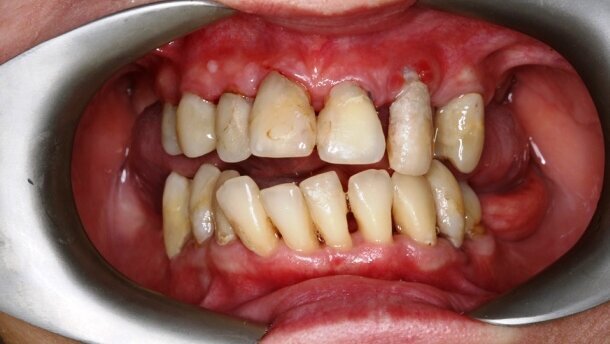

Przedstawiono obraz kliniczny wyjściowy 47-letniej pacjentki ze zdiagnozowaną zaawansowaną uogólnioną chorobą przyzębia, licznymi brakami zębowymi, brakiem protetycznego uzupełnienia zębów bocznych, zmianami okołowierzchołkowymi, niepełnym leczeniem endodontycznym. Pacjentka wymagająca kompleksowego leczenia stomatologicznego. Aby stworzyć wyjściowy plan leczenia, konieczne jest wdrożenie leczenia wstępnego (faza higienizacyjna), aby sprawdzić motywację pacjentki do dalszego leczenia wysokospecjalistycznego i ocenić rokowanie zębów.